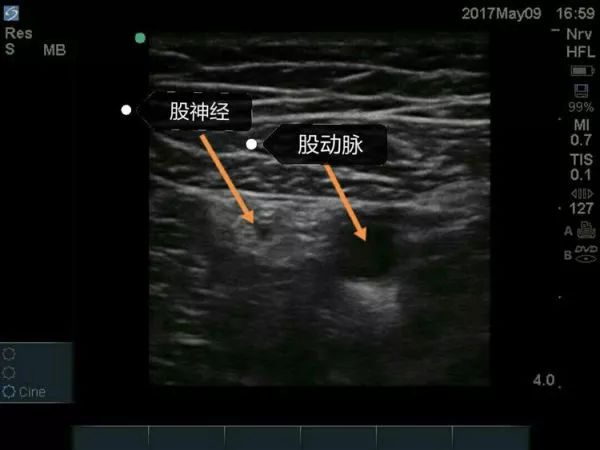

超声引导下股神经阻滞要点

①适应证: 大腿前面、股骨、膝关节手术。

②探头位置: 横向放置、靠近腹股沟。

③目标: 局麻药在股神经周围扩散。

④局麻药: 10-20ml。

超声引导穿刺针刺入股神经表面的肌筋膜

超声引导下股神经阻滞技术可以为髋关节及膝关节置换提供术后镇痛,不影响血流动力学,尤其适用于合并心脑血管疾病的老年患者。